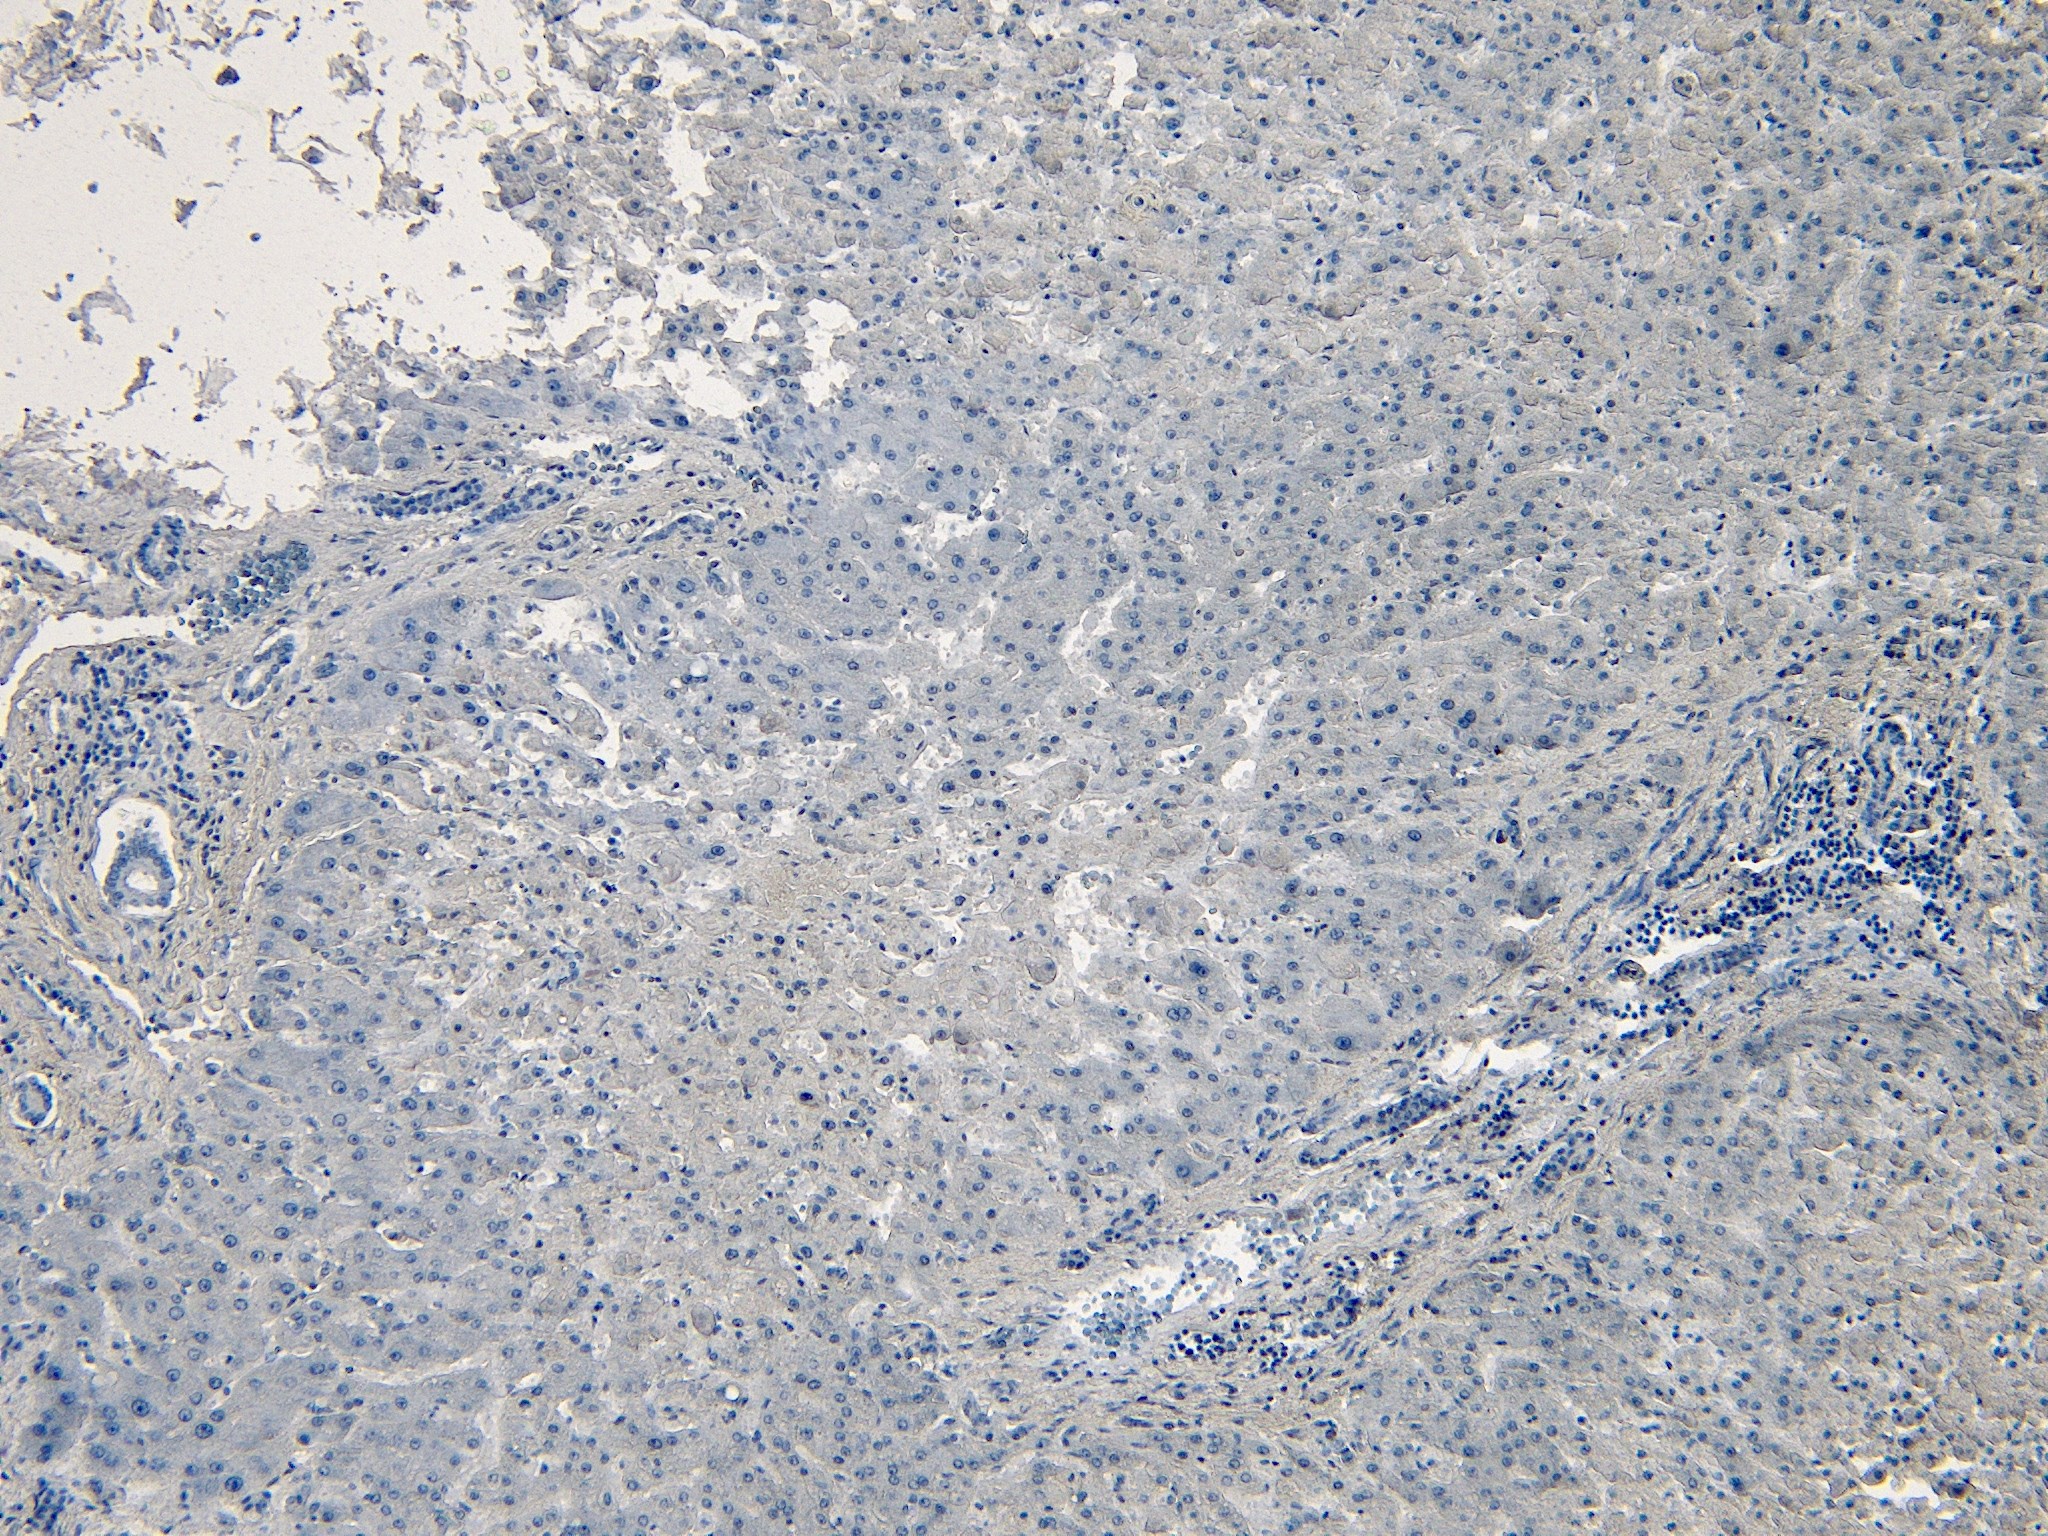

IHC Results Paraffin embedded Human Liver. Recommended concentration: 5-7µg/ml. | |